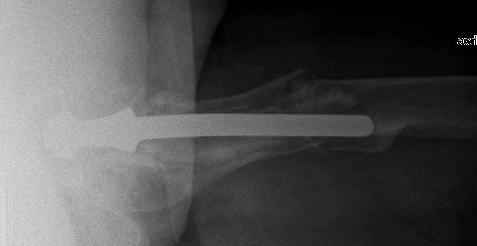

Спасибо за обсуждение. После нескольких дней тракции аппаратом сделали. Попытка закрытой репозиции не удалась из-за смещения по ширине, мешали фрагменты цемента. После их удаления репозиция получилась. Еще убрали немного цемента с ножки по латерльной стороне, чтобы обнажить 40-50 мм ее дистальной части, для плотной посадки гвоздя. Дальнейшее введение гвоздя было несложным. Протез показался нам стабильным в проксимальной части как латерально, так и медиально. Картинки в приложении.

THX for the discussion. After few days of traction by ex-fix the surgery was performed. An attempt of closed nailing was unsuccesful because of fragment translation, which was blocked by cement fragments. After removal of broken cement pieces reduction was reached "automagically". Also some cement from lateral part was removed by

chisel to expose distal 40-50 mm of the stem to allow tight fit of the nail. Further fixation by the nail was pretty easy and straightforward. Images attached. The stem looked stable in its proximal part both laterally and medially. Comments/critics are welcome.